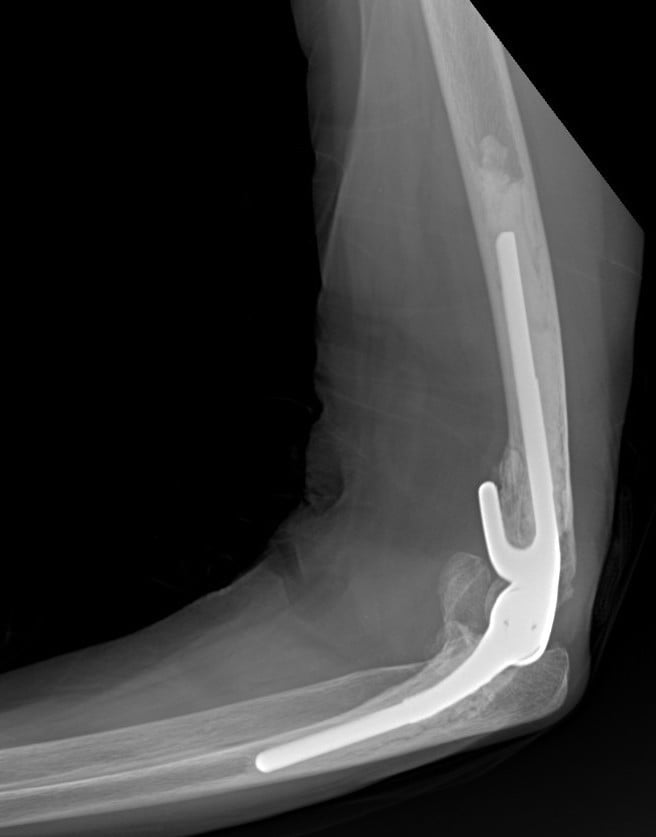

Η αρθροπλαστική αγκώνα είναι η χειρουργική επέμβαση που περιλαμβάνει την αντικατάσταση των φθαρμένων επιφανειών του αγκώνα με μεταλλικά εμφυτεύματα. Υπάρχουν 2 κύρια είδη αρθροπλαστικής αγκώνα: η ολική αρθροπλαστική αγκώνα (ΤΕΑ, ή total elbow arthroplasty) και η ημιαρθροπλαστική. Στην ολική αρθροπλαστική αντικαθίστανται και οι δύο αρθρικές επιφάνειες με μεταλλικές προθέσεις που αρθρώνονται μεταξύ τους. Χρησιμοποιείται κυρίως στην οστεοαρθρίτιδα που συνήθως προκαλεί την φθορά και των 2 αρθρικών επιφανειών. Στην ημιαρθροπλαστική (“hemi”), αντικαθίσταται με πρόθεση μόνο η μία από τις αρθρικές επιφάνειες αυτή του βραχιονίου. Η ημιαρθροπλαστική χρησιμοποιείται κυρίως σε πολύ περιφερικά κατάγματα του περιφερικού βραχιονίου, που δεν δύνανται να επιδιορθωθούν με εσωτερική οστεοσύνθεση.

Το χειρουργείο γίνεται σε πλάγια ή ύπτια θέση. Ο χειρουργός πραγματοποιεί μία τομή στο πίσω μέρος του αγκώνα και στη συνέχεια βρίσκει και προστατεύει το ωλένιο νεύρο. Οι φθαρμένες αρθρικές επιφάνειες κόβονται με ειδικούς οδηγούς και οι προθέσεις στερεώνονται με τη βοήθεια τσιμέντου, το οποίο σκληραίνει σε περίπου 10 λεπτά. Το τραύμα κλείνεται κατά στρώματα και εφαρμόζεται μία χαλαρή περίδεση. Το άκρο τοποθετείται σε μία ανάρτηση.